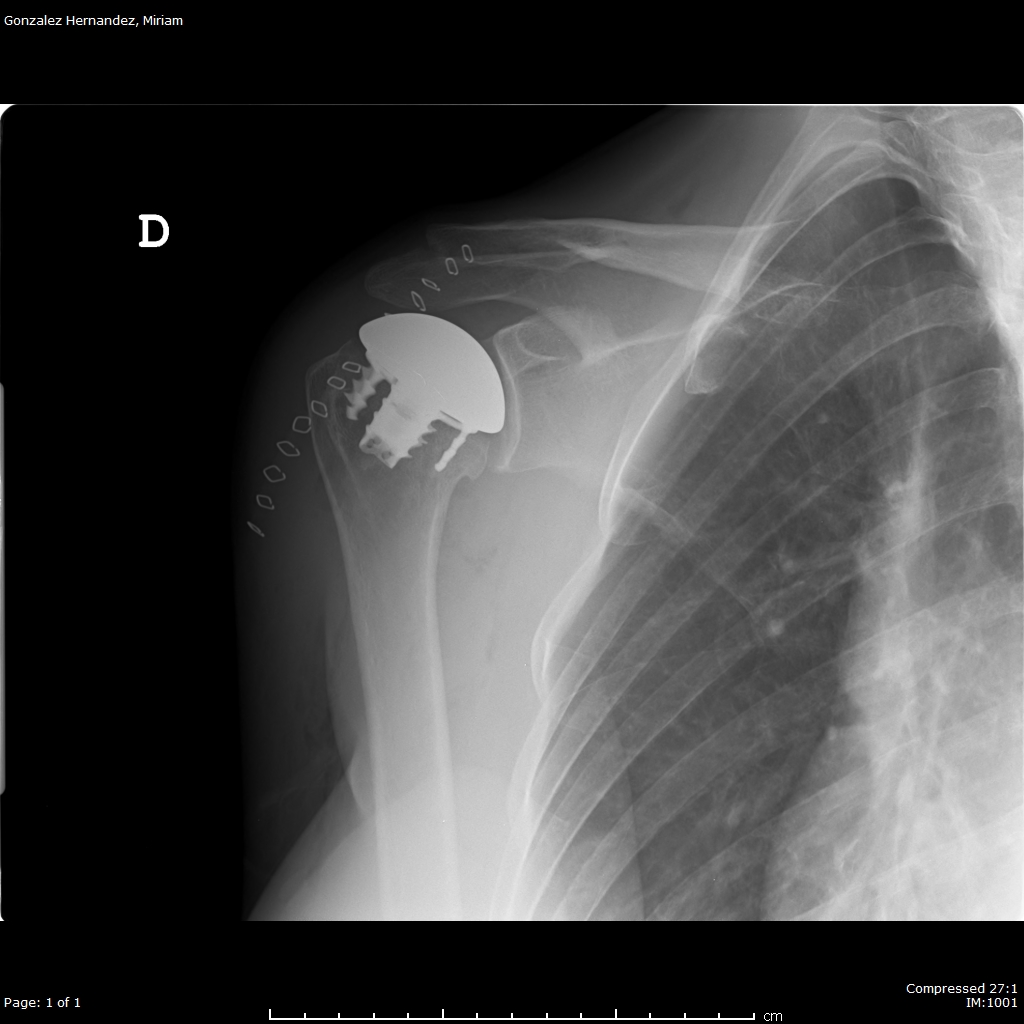

Davant d'aquesta situació, l'opció per millorar el dolor i la mobilitat és la implantació d'un pròtesi de cobriment de la superfície articular.

Aquesta opció és l'aconsellable en un pacient jove i amb aquest diagnòstic en ser la que implica menys pèrdua d'os.

Després del procés postoperatori, la pacient va manifestar una millora progressiva del dolor i va recuperar la mobilitat de l'espatlla.